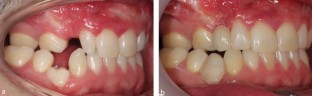

Primary molar teeth that are retained beyond their exfoliation pose a clinical decision-making challenge for dental teams. The retention of these teeth may be due to absence of a permanent successor. As a result, careful planning is required to determine if retention or extraction is necessary. This article aims to discuss the prevalence of retained primary molars, assessment and treatment planning considerations, from both orthodontic and restorative perspectives.

Explains considerations for retaining primary molars and methods of utilisation.

Explains considerations for extraction of primary molars and consequences if retained, such as infraocclusion.